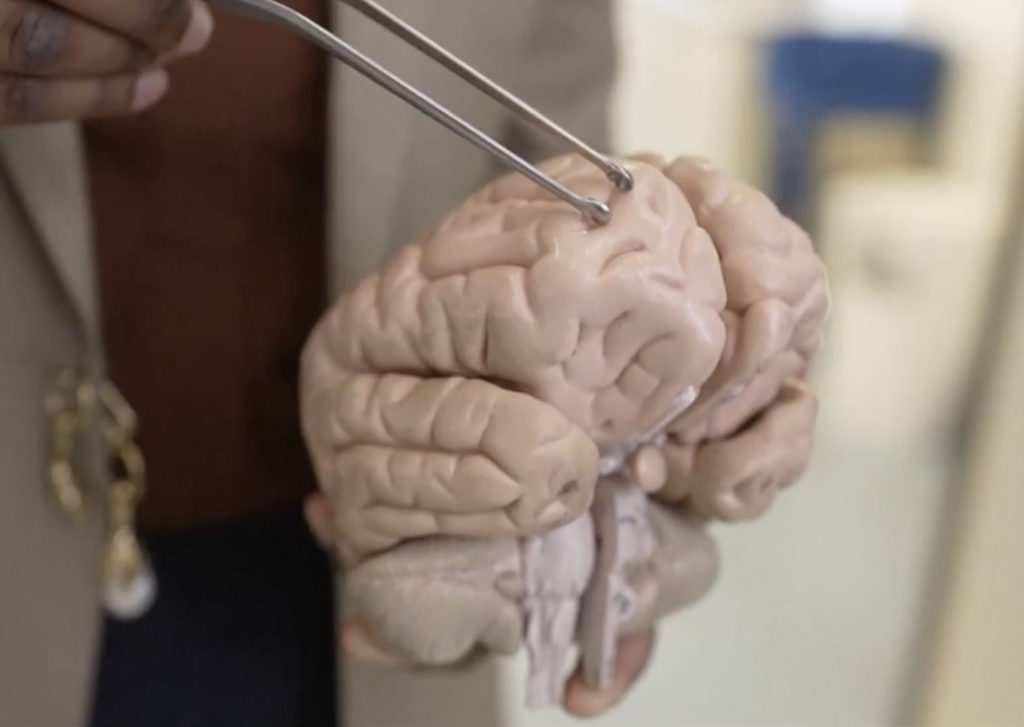

Dr. Bandi performed brain surgery on a 64-year-old woman and was taken aback when she pulled out an 8-centimetre (3-inch) long parasitic roundworm that was still wriggling between her forceps.

The revelation sparked intense curiosity among medical professionals to identify the parasite.

“We were able to send the live wiggling worm to him, and he was able to look at it and immediately identify it.”

The parasite was identified as Ophidascaris Robertsi, a roundworm typically found in pythons, after a thorough examination and molecular tests.